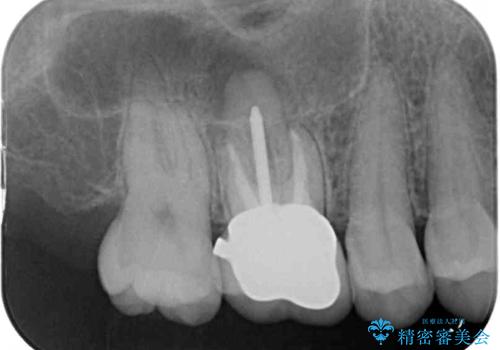

処置後、下顎の膿の出口はすぐに消えましたが、レントゲン写真からも分かるとおり、歯根途中に穴が開いており、充填材が歯根外にはみ出していました。数ヶ月経過を見たところ、特に異常は認められなかったため、補綴治療を行いました。